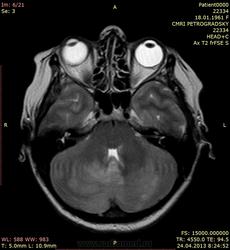

Лептоменигиальные метастазы

Пациентка 53 лет. Постепенно развилось нарушение сознания, на момент обследования в сопоре. В анамнезе - комбинированное лечение рака молочной железы.

Отдельный интерес представляет то, что происходит в мозжечке и левой теменной доле - чем именно представлены зоны изменения сигнала в ткани мозга? Термин "отек" все же несколько неконкретен. Тем более, что он осложнился в нашем случае окклюзией и вклинением.

Является ли этот отек венозным инфарктом, возникшим в результате поражения путей венозного оттока опухолевой тканью? Интересно мнение коллег.